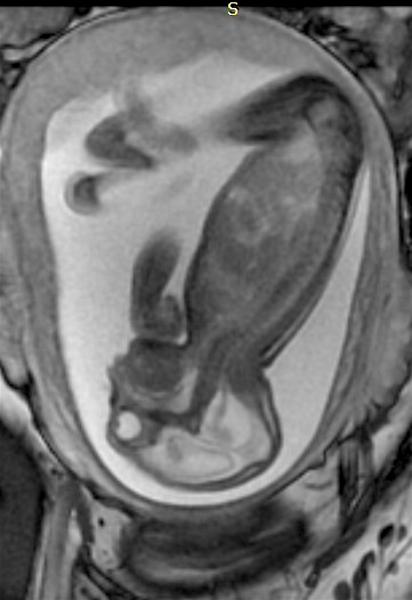

Below is a collection of prenatal ultrasound pictures from the Imaging Technology News (ITN) archive. Use the arrows to ...